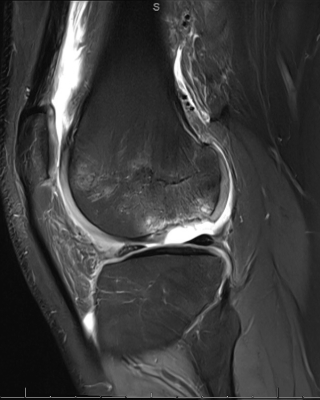

“We decided to try the live allograft first because, while we planned for two surgeries, we wondered if we could achieve something meaningful in a single-stage procedure under a single anesthesia event in a pediatric patient,” says Dr. Kannan. “Three months post-surgery, we obtained an MRI and noted the area we grafted healing beautifully — cartilage and underlying bone reconstituted, matching his femoral condyle contour perfectly. At three months, that’s remarkable.”